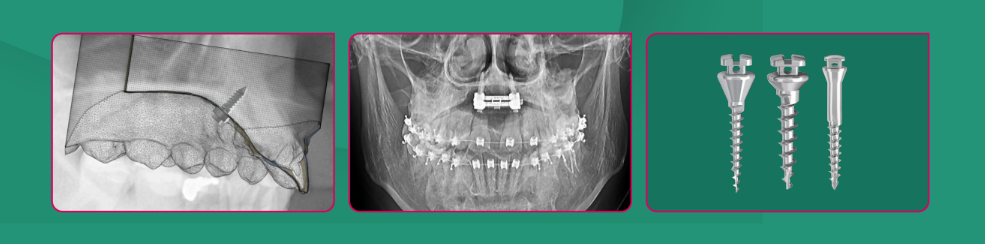

Szkolenie wprowadzające z wykorzystaniem kompletnego systemu implantologicznego HDC oraz śrub Spider Screw® 🔩

Szkolenie przeznaczone dla ortodontów chcących wprowadzić do swojej praktyki przewidywalne protokoły leczenia z wykorzystaniem zakotwienia szkieletowego

Szkolenie obejmować będzie ćwiczenia z zakresu zakotwienia międzykorzeniowego jak i poza zębowo-wyrostkowego.

• 2 implanty podniebienne z użyciem szablonu

• 2 implanty międzykorzeniowe w szczęce: jeden przy użyciu szablonu, drugi „free hands”

• implant zygomatyczny w obszarze kresy skośnej żuchwy z użyciem szablonu

• 2 implanty miedzykorzeniowe w żuchwie w sytuacji wystąpienia powikłania utraty implantu.